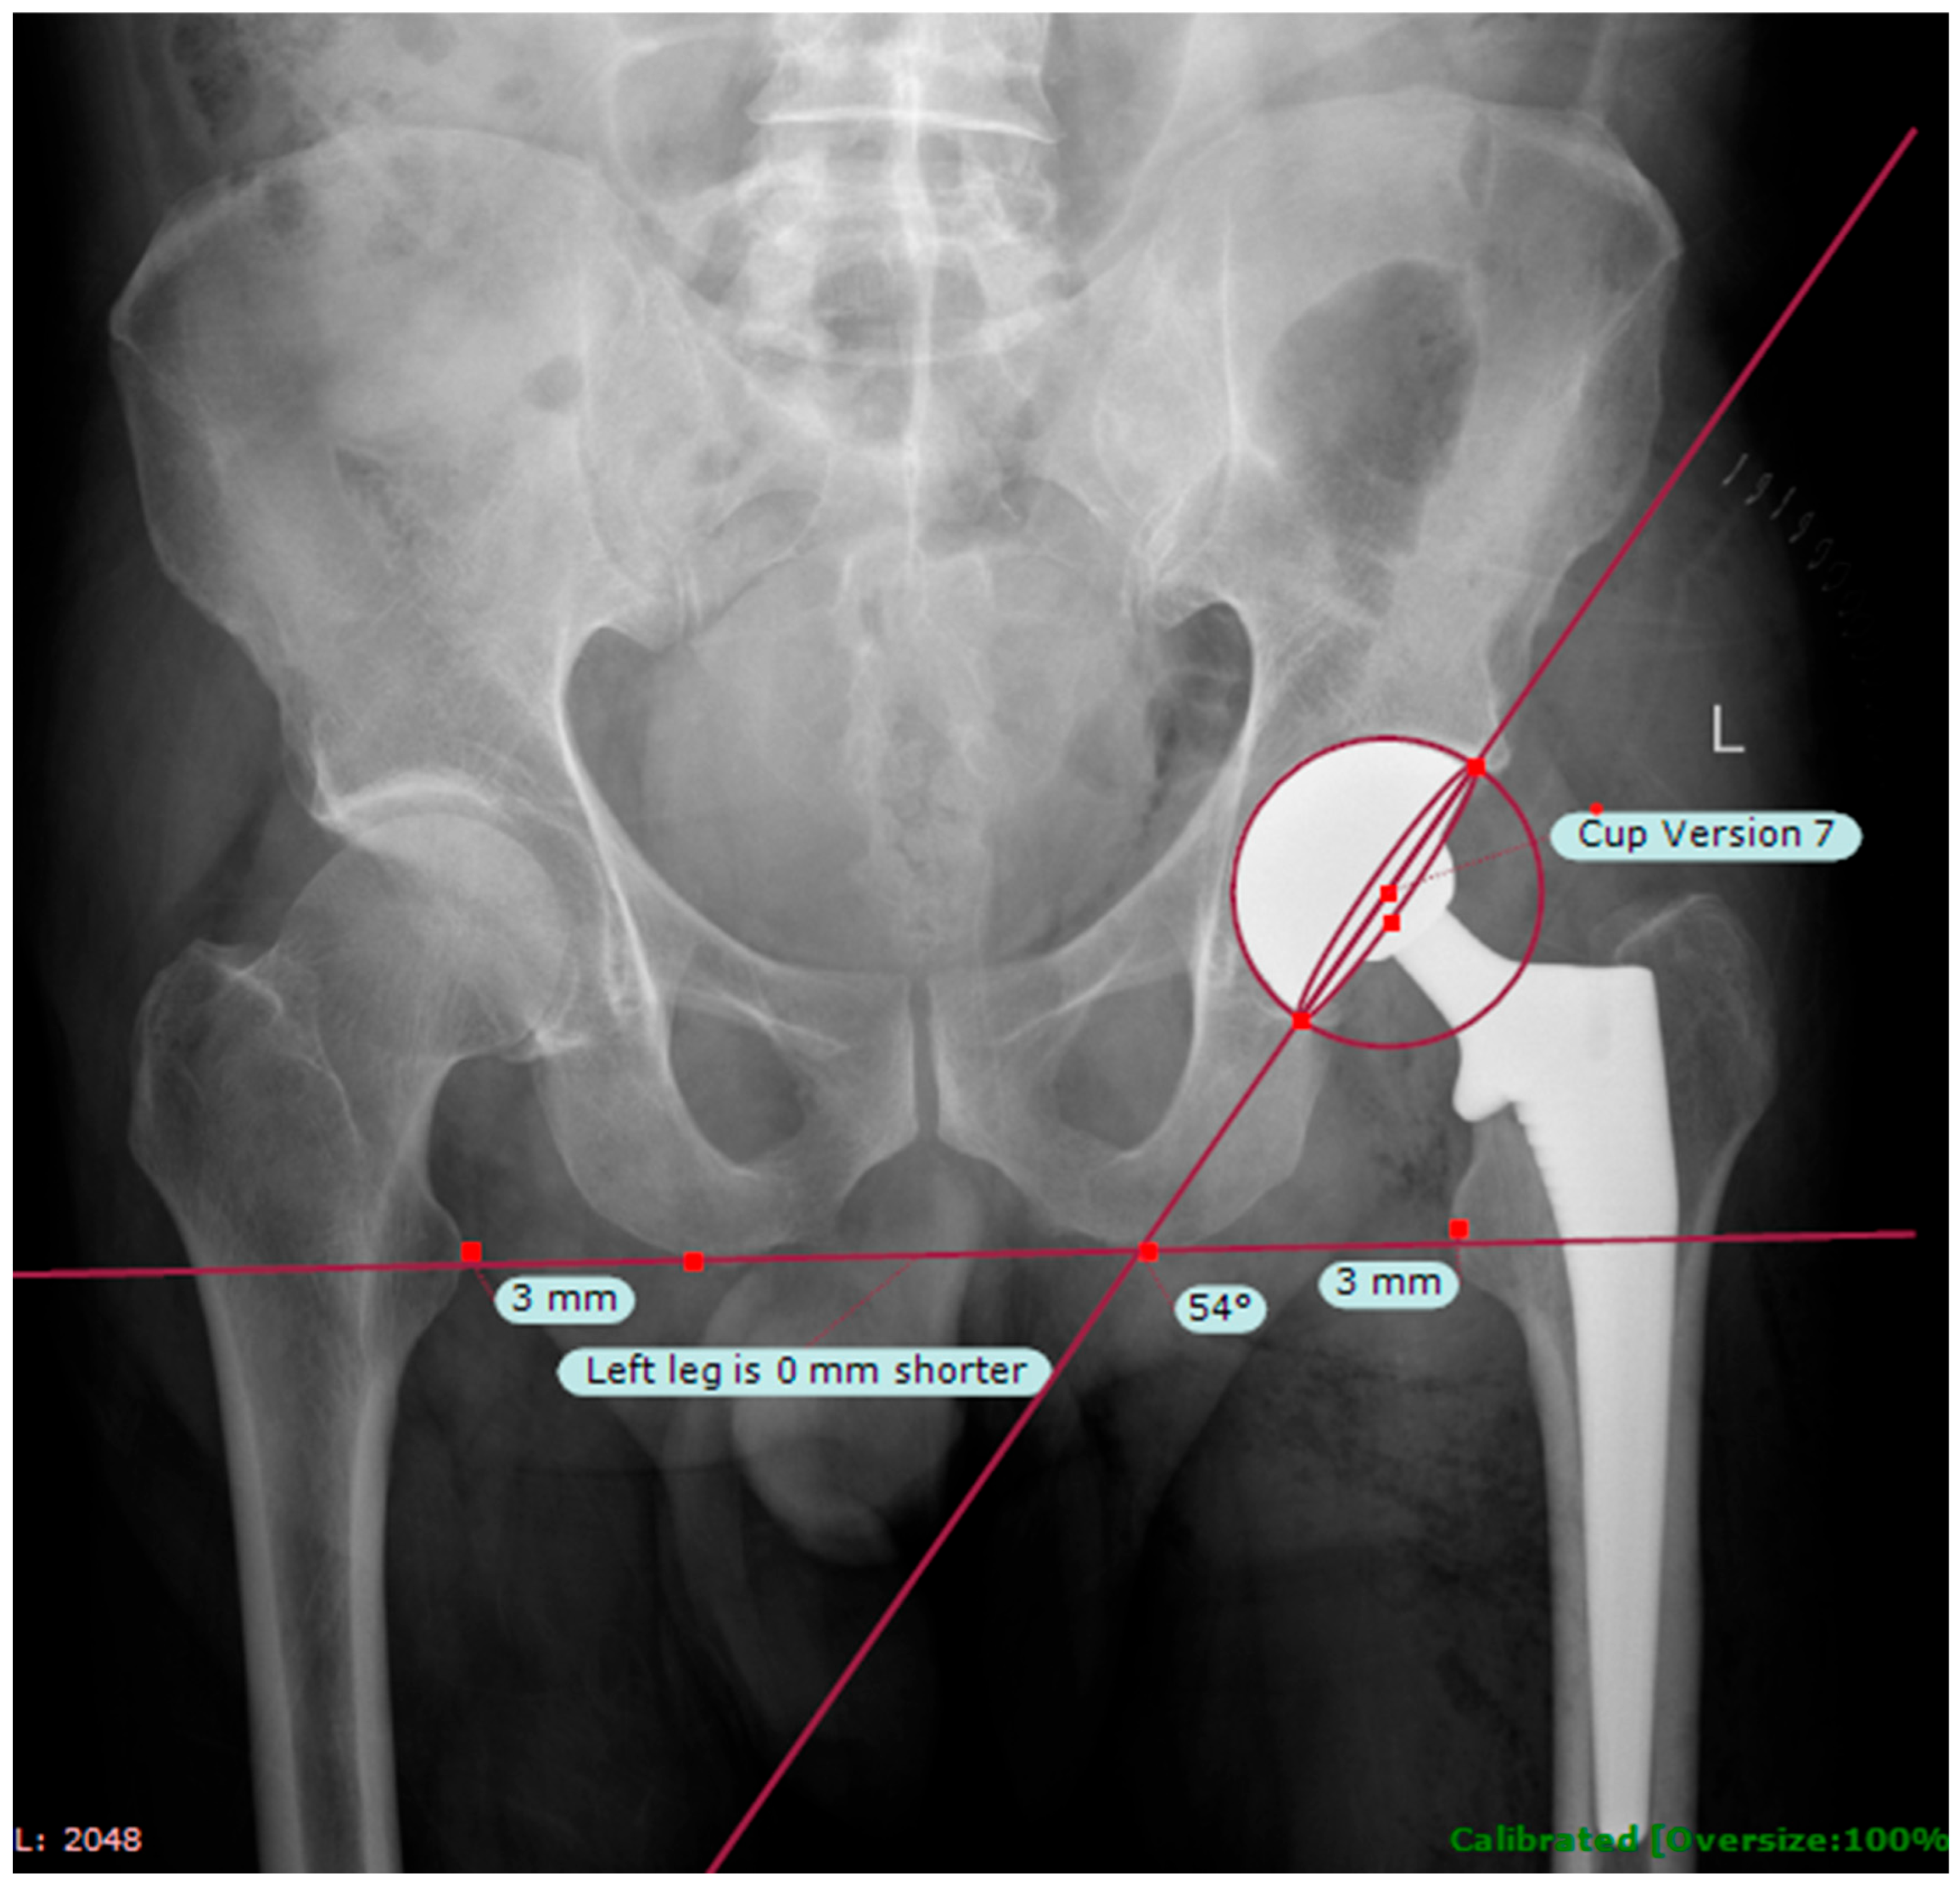

- Kumar, P.G.A.; Kirmani, S.J.; Humberg, H.; Kavarthapu, V.; Li, P. Reproducibility and accuracy of templating uncemented THA with digital radiographic and digital TraumaCad templating software. Orthopedics 2009, 32, 815. [Google Scholar] [CrossRef] [PubMed]

- Westacott, D.J.; McArthur, J.; King, R.J.; Foguet, P. Assessment of cup orientation in hip resurfacing: A comparison of TraumaCad and computed tomography. J. Orthop. Surg. Res. 2013, 8, 8. [Google Scholar] [CrossRef] [PubMed]

| Mean Cup Anteversion, Deg (SD) | 11.34 (7.03) | 14.06 (5.34) | 0.006 |

| Mean Femoral Offset, mm (SD) | 44.92 (7.34) | 45.31 (5.88) | 0.697 |

| Mean LLD, mm (SD) | 0.72 (6.52) | 1.64 (7.30) | 0.384 |